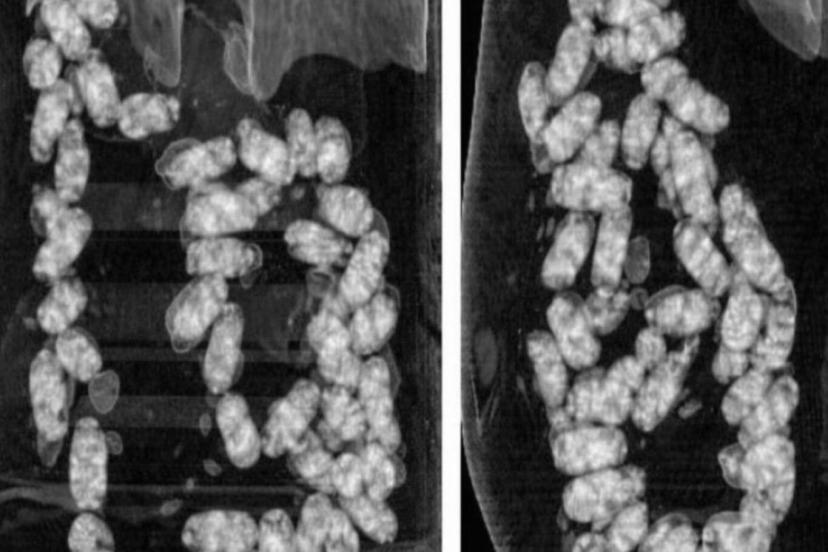

Narkotik Suçlarla Mücadele Şube Müdürlüğü ekiplerince yurt dışından İzmir’e "yutmak" suretiyle uyuşturucu madde getirilmesi üzerine operasyon başlatıldı.

Yapılan teknik ve fiziki takip sonucunda kimlikleri tespit edilen şahıslar, İzmir Adnan Menderes Havalimanı’nda yakalandı.

Şüpheliler üzerinde yapılan iç beden muayenesinde, 105 kapsül halinde yutulmuş vaziyette toplam 965 gram metamfetamin ele geçirildi.